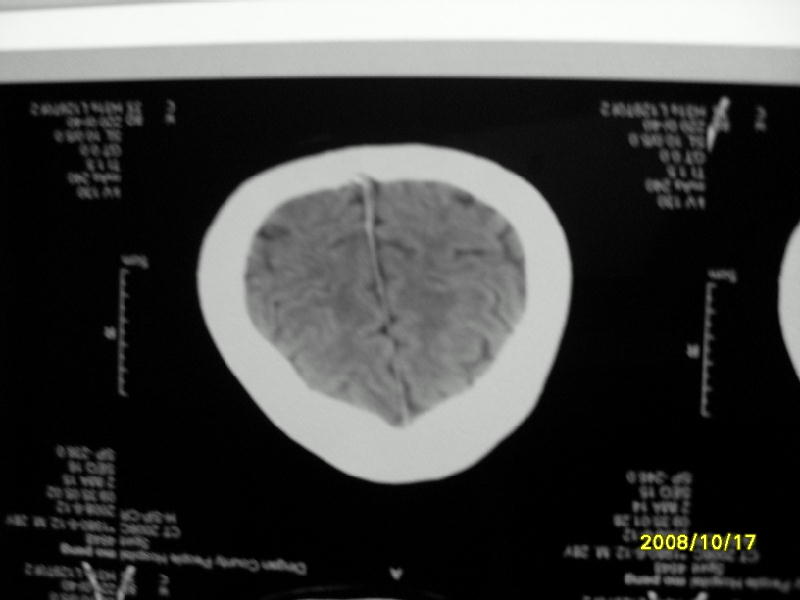

检查名称:     ct颅脑平扫           男     28岁

表现:左顶叶见斑点状致密影。边缘清,大小约0。3*1。0cm,余脑实质密度及灰白质结构示见异常。脑室系统大小,形态,密度未见异常。脑沟。脑裂。脑池未见异常密度影。中线结构无移位。

印象:左顶叶少许钙化灶

左顶叶见斑点状致密影。边缘清,大小约0。3*1。0cm,余脑实质密度及灰白质结构示见异常。脑室系统大小,形态,密度未见异常。脑沟。脑裂。脑池未见异常密度影。中线结构无移位。

印象:左顶叶少许钙化灶。